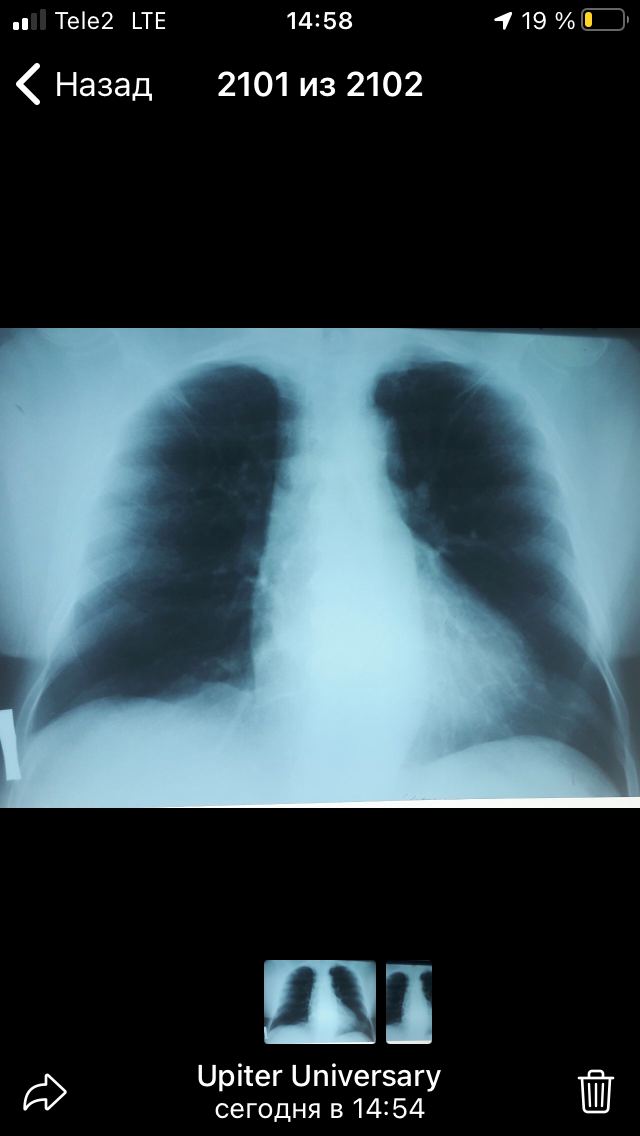

Либо у меня экраном не то, либо снимок суперэкспонирован. Ничего подозрительного не вижу.

Жесткий, переснять

Там еще 2 фото

Нечего из 7 признаков ТЭЛЫ невидно  , ну то что талия в лево расширена и тень дуги аорты уплотнена то как бы и все

я бы начал свой доклад с того, что рентген симптомы при ТЭЛА неспецифичны и не особо чувствительны, по некоторым данным доходя до 30% чувствительности в зависимости от вторичных признаков, как ателектаз или выпот и тд

Переделать , массивная дама .....